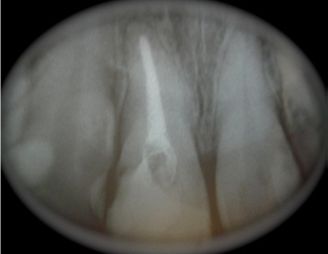

Al estudio RX se aprecia un conducto amplio, sobre todo en su tercio cervical con paredes bastante delgadas. (Fig. 1)